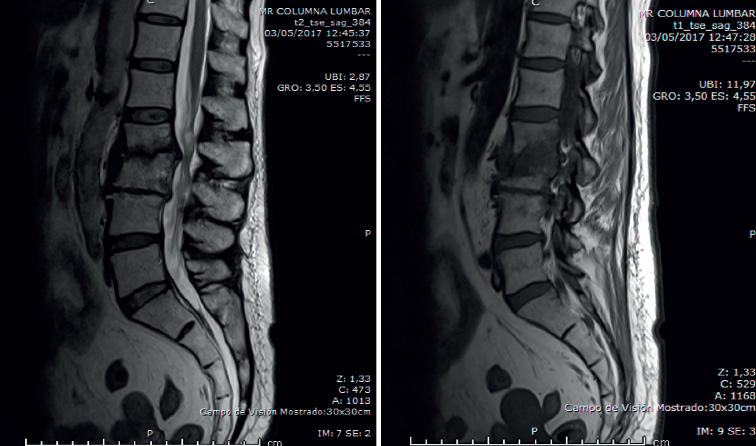

Figura 4. Resonancia magnética a los 3 meses del ingreso. Sagitales T2 y STIR.

En la RM lumbar (Figura 4) se observaba desaparición de los abscesos preexistentes. Discopatía evolucionada.